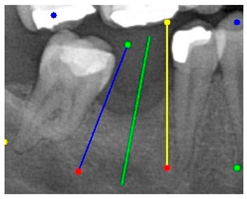

| Comparison with dentist’s ground truth (black line) and our framework (green line) | ||||||

| Validation Image 1–6 | ![]() | ![]() | ![]() | ![]() | ![]() | ![]() |

| MSE | 3.59 | 1.29 | 0.41 | 0.80 | ||